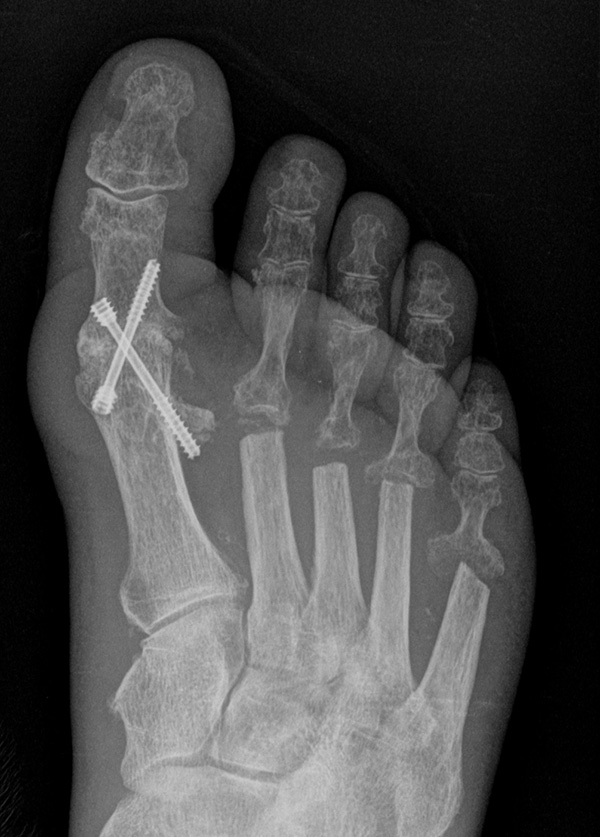

Die Operation nach Hoffmann-Tillmann (Abb. 4) ermöglicht durch die Resektion der Metatarsaleköpfe die Reposition der Zehen, da hierdurch der notwendige Platz geschaffen wird (Tillmann 1990). Meist sind nicht nur die knöchernen Strukturen der Metatarsaleköpfe destruiert, auch das plantare Polster ist disloziert, regelmäßig kommt es zur Ruptur der plantaren Platten mit Destruktion der Kapsel-, Band- und Sehnenstrukturen (Tillmann 2009) 6. Häufig findet man ausgeprägte Rheumaknoten oder Bursitiden plantar. Durch die breite, querovaläre Hautexzisionaus dem Vorfußballen werden plantare Schwielen entfernt, später beim Hautverschluß werden die plantaren Strukturen durch die plastische Dermatodese wieder in die Belastungszone reponiert.

Es sollten immer alle MT Köpfe II-V reseziert werden, um einen harmonischen Metatarsale Index mit genauer Längenabstimmung herzustellen und keine Druckspitzen durch überlange Metatarsalia zu provozieren. Die kann in Einzelfällen bedeuten, dass ein weniger destruiertes Gelenk zwischen oder am Rand der metatarsalen Reihe geopfert werden muss. Die Operation nach Hoffmann-Tillmann wird meist ab LDE Stadium IV und V indiziert (Tabelle 1).